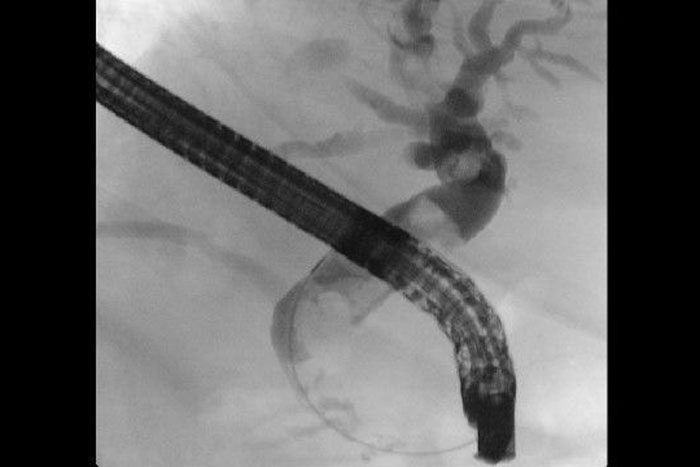

ERCP - Endoskopisch retrograde Cholangiopankreatikographie

Untersuchung des Gallen- und Pankreasganges

Darstellung eines Bauchspeicheldrüsenganges bei chronischer Entzündung